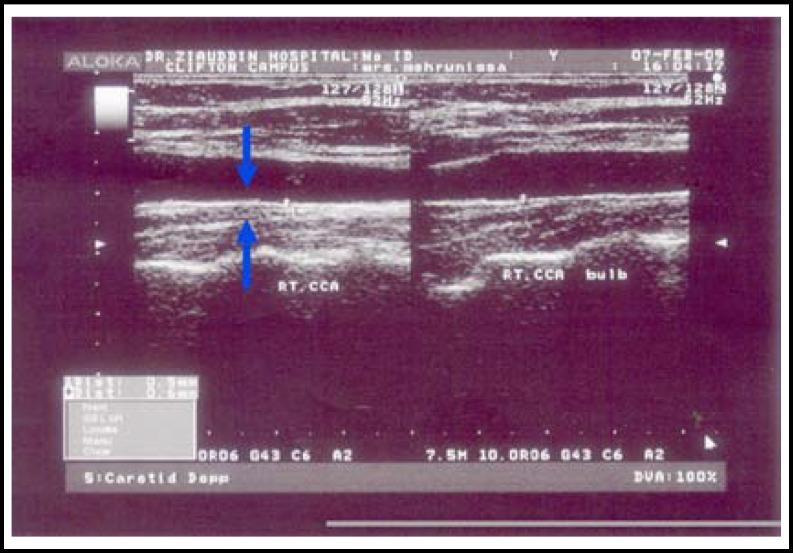

Determination of site-specific carotid-intima media thickness: common -carotid artery and carotid bifurcation in hypercholesterolemia patients.

Fifty patients with hypercholesterolemia and twenty controls were selected after getting informed consent regarding the investigation of carotid- intima media thickness by B-mode ultrasound. All the patients of hypercholesterolemia with LDL-C > 160mg/dL had family history of coronary artery diseases. This procedure was carried out in the Radiology Department of Dr. Ziauddin Hospitals. Measurement of carotid -intima media thickness, B-mode ultrasonography of common carotid artery, carotid bifurcation and internal carotid artery (left and right carotid arteries) was performed with Toshiba (M# SSA-580A/E2) ultrasound scanner with linear probe. The posterior or far wall of the carotid artery is, the distance between the leading edge first bright line (lumen -intima interface) and the leading edge of the second bright line (media-adventitia interface) of far wall was recorded as intima -media thickness. The average mean of six segments of intima-media thickness was taken as mean CIMT of right and left common carotid, bifurcation and internal carotid arteries.

Maximal CIMT was significantly increased at sites common carotid, carotid bifurcation and internal carotid arteries in fifty patients with hypercholesterolemia as compared to controls. At carotid bifurcation mean of maximal CIMT was (0.9+ 0.3mm). Range of maximum CIMT in hypercholesterolemia patients was (0.8- 3.3mm) and in controls (0.4- 0.8 mm). The thickness was more frequently increased at site of bifurcation.